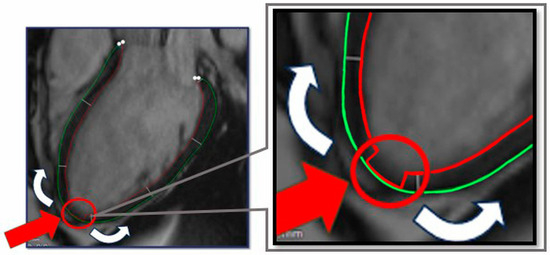

Figure 3.

Contour preparation for OptiLayer analysis. The green circle indicates the epicardial-, the red circle refers to the endocardial boundary. The red arrow indicates the aligned epicardial and endocardial contours at the apex of the heart, which represents the origin of the wall thickness analysis from the apical to the basal segments (white arrows).

(A): Visual representation of the OptiLayer method in schematic chart. The red line indicates the endocardial-, the green line shows the epicardial contours. The dark green area represents the left ventricular wall. 1: Detection of the cardiac apex; 2: Measurement direction from the base through the apex to the contralateral base. The gray lines indicate the automated measurement between the epicardial and endocardial contours; 3: The sequence based on the 100 auto-measured wall distances. Values close to zero indicate the cardiac apex, which is detected by the OptiLayer. 4: Accurate wall thickness assessment based on anatomical segmentation. The measurement series from the apex to the base is divided into three parts, yielding the wall thicknesses of the basal, mid, and apical segments. RA: right atrium; LA: left atrium; RV: right ventricle; LV: left ventricle; s17: segment 17; Basal: basal third; Mid: middle third; Apical: apical third. (B): Front end of the OptiLayer program. This screenshot shows the user surface in use, after loading the images, as shown in the left gray panel with test patients. The numbers on the bullseye LV model represent the wall thickness of each segment in mm. Red segments indicate when wall thickness is under 5 mm. Sg: Segment; A2ch: two chamber view; A3ch: three chamber view; A4ch: four chamber view; 3rd: third; Mid: middle.

According to this, the simplest way to mark the apex of the heart in this 100-distance measurement sequence is to set the contour distance values close to 0 mm in the area of the apex (segment 17). This can be done by touching the QMASS automated endocardial contour to the epicardial contour in the area corresponding to the apex of the heart, and the QMASS will generate measurements close to 0 mm in this area (roughly 4–8 measurements).